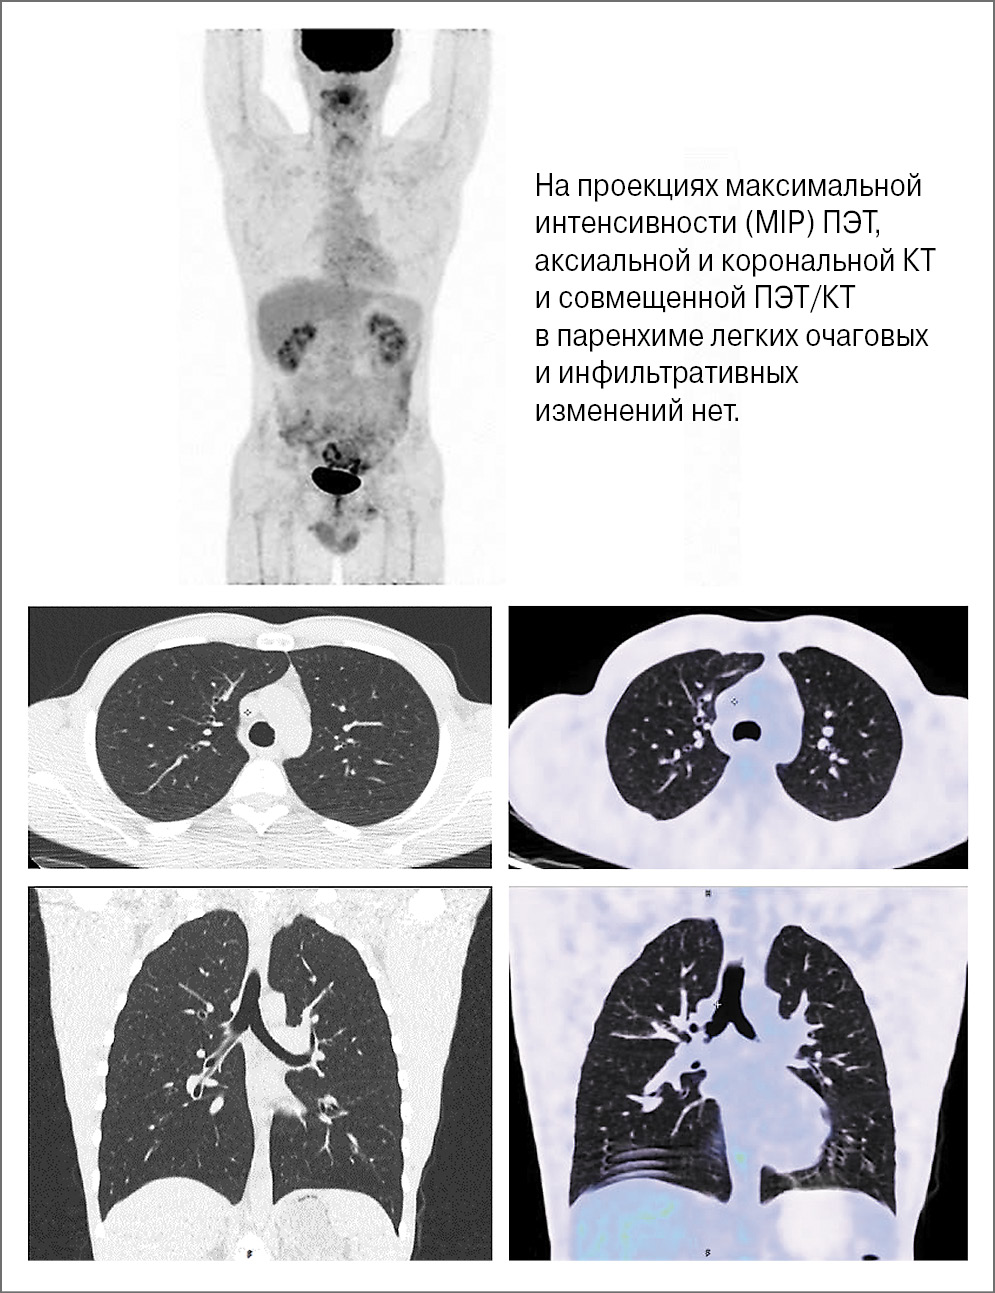

На этом этапе лечения проводилась ПЭТ/КТ с 18F-ФДГ с интервалом 4–5 мес. При этом каких-либо рентгенологических проявлений легочной патологии не обнаружено (рис. 1).

Рис. 1. Пациент П., 37 лет. Через 12 мес после начала поддерживающей терапии ритуксимабом.